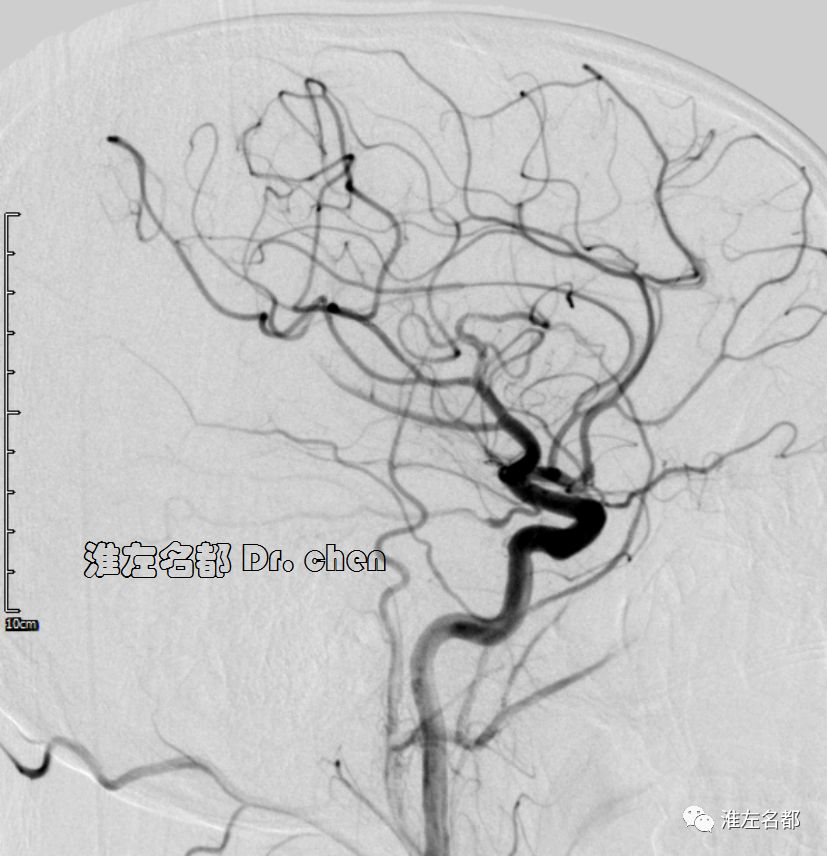

△头颅CTA:左侧前循环管腔通畅,未见明显狭窄。

△3D-TOF-MRA:左侧大脑中动脉M1段和前动脉A1段管腔显影不规则;左侧大脑中动脉分支显影较对侧稀疏(考虑和大面积梗死后供血需求降低有关)。